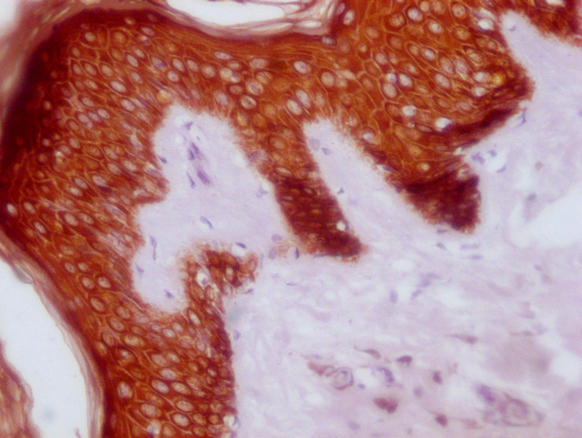

Human skin tissue

1:100